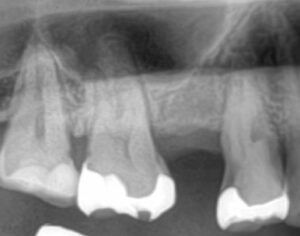

Before/After X線写真

治療前後のX線画像をご紹介します。

(画像:xray_rc1.jpg Before/After X線写真比較)

治療前には根尖周囲に淡い透過像(炎症の兆候)が見られましたが、

治療後は根管が適切に封鎖され、再感染のリスクが大きく軽減された状態が確認できます。